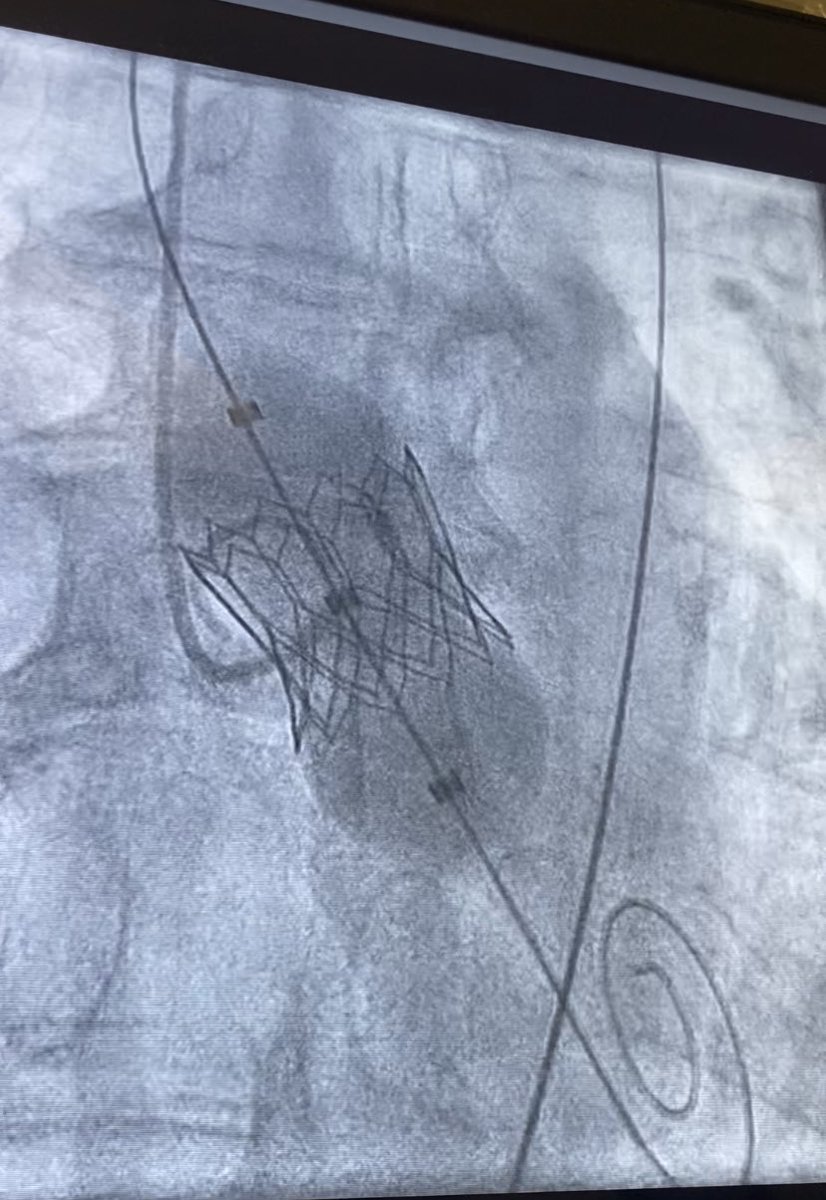

Successful implant of COLIBRI heart valve (first in UK!) Honoured to have Dr David Fish from Houston TX Medical Centre to support the case. Barts TAVI Michael Mullen @BartsHospital Mick

Successful implant of COLIBRI heart valve (first in UK!) Honoured to have Dr David Fish from Houston TX  Medical Centre to support the case. <a href="/BartsTAVI/">Barts TAVI</a> <a href="/bartstructural/">Michael Mullen</a> @BartsHospital <a href="/Ozkor/">Mick</a>